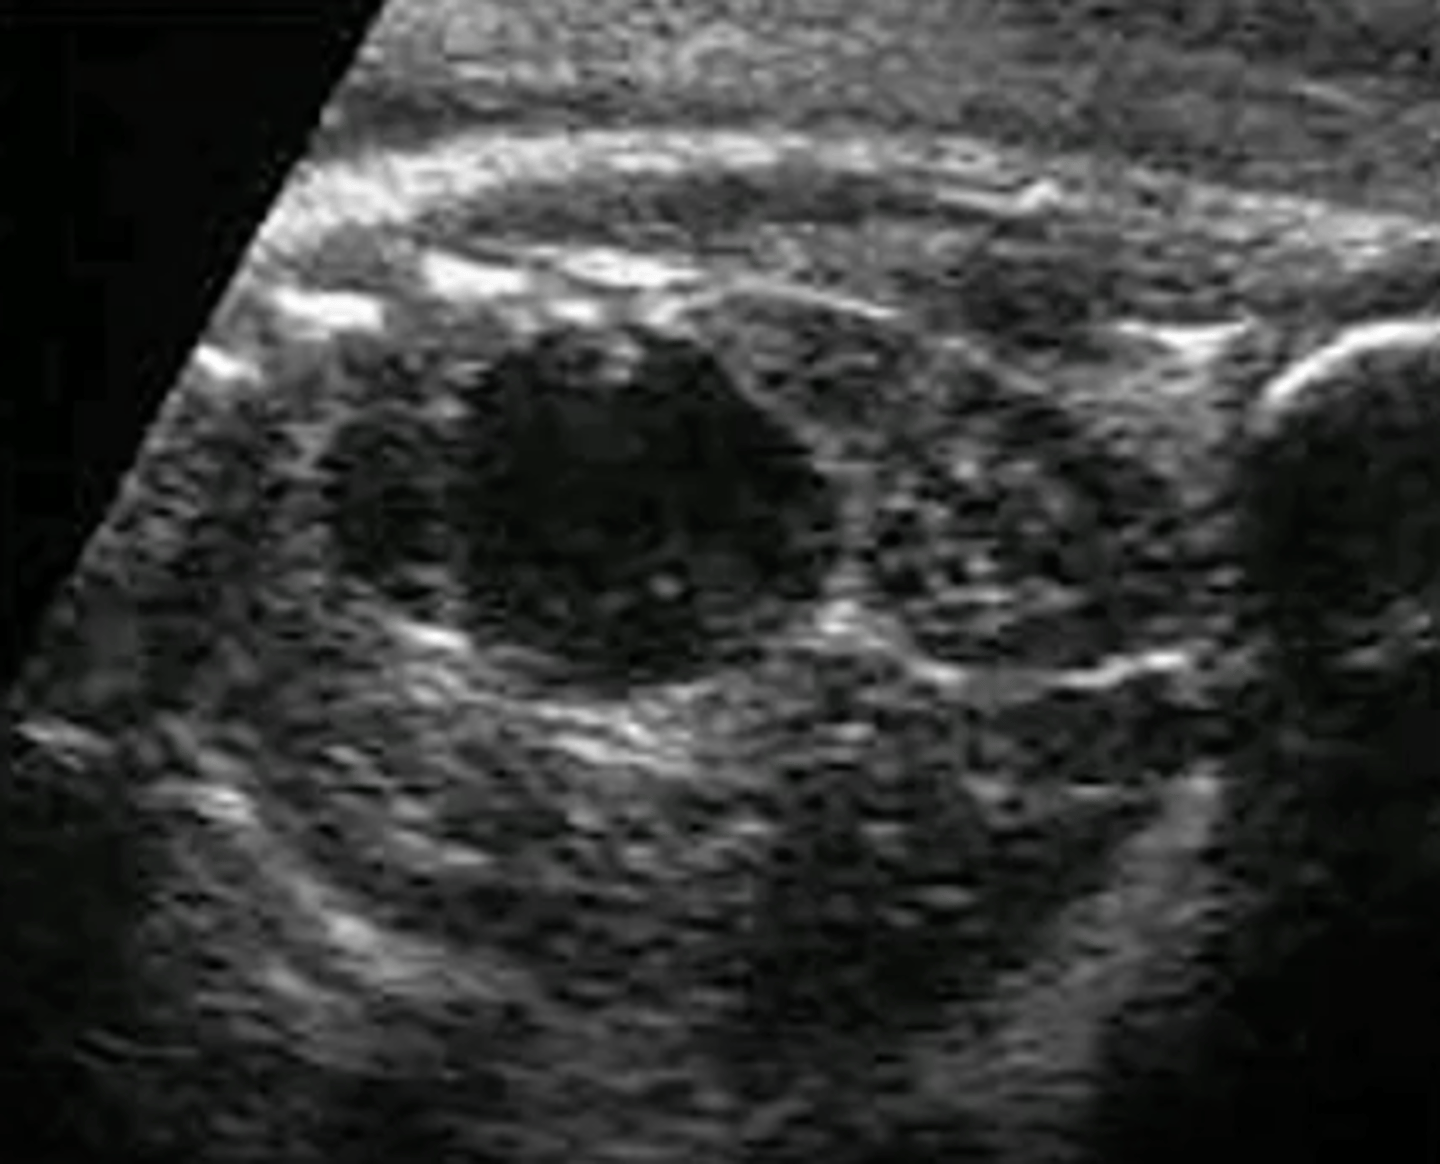

What is the typical sonographic appearance of a neuroblastoma?

Heterogeneous, hyperechoic mass with poorly defined margins

What will Color Doppler demonstrate on a neuroblastoma?

Capsular flow